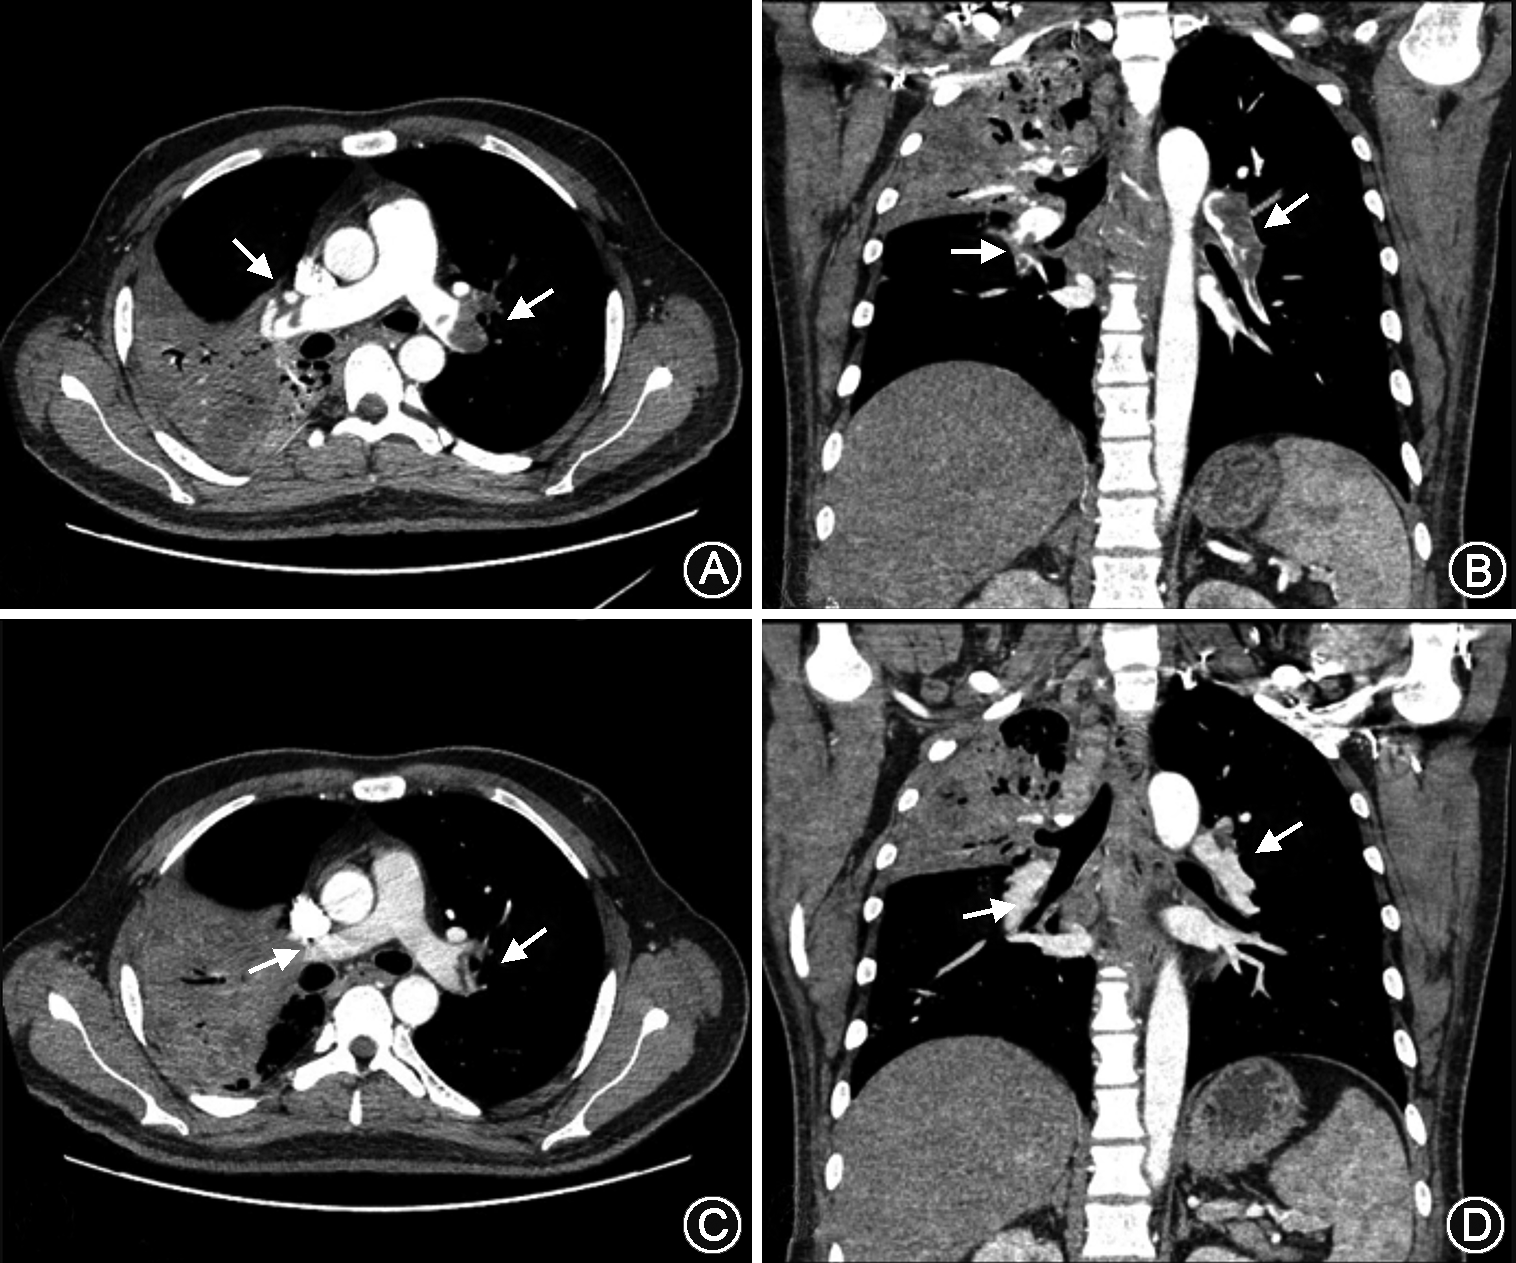

急查血气分析:pH值为7.420,氧分压(PaO2)57.0 mmHg,二氧化碳分压(PaCO2)29.1 mmHg,吸入氧浓度(FiO2)为41%;N-端脑利钠肽前体5180 ng/L;血常规:白细胞7.3×109/L, 红细胞5.72×1012/L,血红蛋白140 g/L,血小板262×109/L;凝血功能:凝血酶原时间12.8 s,凝血酶时间18.4 s,活化部分凝血酶时间35.7 s,国际标准化比值:1.10,D-二聚体18 070 μg/L,纤维蛋白原5.14 g/L;床边胸片排除自发性气胸。同步完善下肢血管B超:右侧腘静脉内几乎充满中等样回声,心脏彩超:射血分数(EF):55%,右心增大,肺动脉高压(54 mmHg),三尖瓣、肺动脉瓣轻度返流。左室收缩功能正常低值。胸部增强CT扫描示左右肺动脉主干及分支充盈缺损(图1,2)。

2. 急性肺血栓栓塞症(中高危):患者住院期间突发胸闷气急;查D-二聚体18 070 μg/L,胸部增强CT扫描示左右肺动脉主干及分支充盈缺损,心脏彩超:右心增大,肺动脉高压(54 mmHg),N-端脑利钠肽前体5 180 ng/L;患者血流发动力学稳定。

经治疗4 d后患者胸闷气急逐步缓解。复查双下肢深静脉B超:右侧腘静脉内中等样回声(栓子形成,大小约20 mm×3 mm)。双下肢股静脉、左侧腘静脉血流通畅。凝血功能:D-二聚体3 260 μg/L血气分析:pH值为7.463,氧分压(PaO2)69.1 mmHg,二氧化碳分压(PaCO2)37.4 mmHg,吸入氧浓度(FiO2)为21%。治疗半个月后复查胸部增强CT提示患者左右肺动脉主干及分支少许充盈缺损。患者病情稳定,带药口服抗结核及抗凝药物出院。